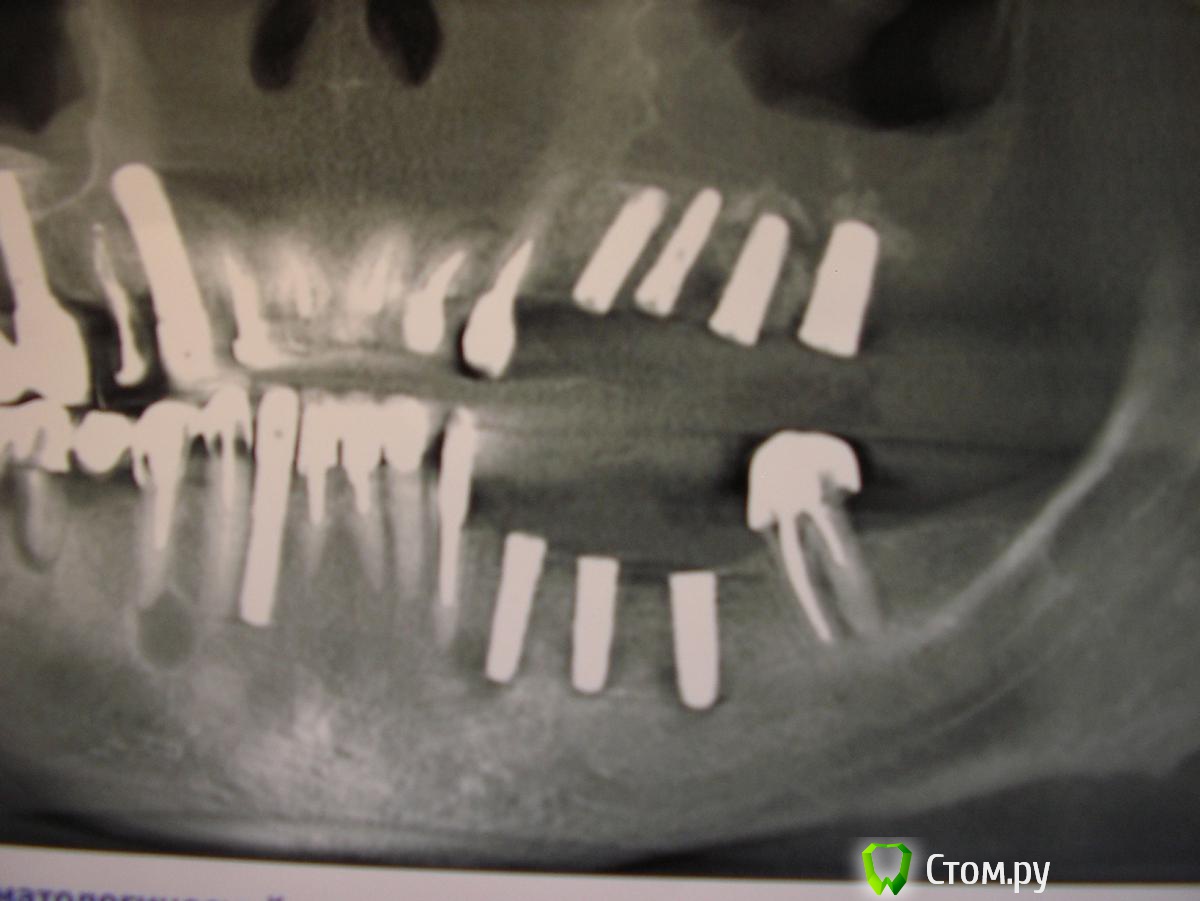

Alvina Опубликовано 31 июля, 2014 Автор Поделиться Опубликовано 31 июля, 2014 (изменено) Ну вот, сделали мне нарезку из прицельной КТ верхних имплантов. Очень бы хотелось услышать мнение специалистов.New Документ Microsoft Word.doc Изменено 31 июля, 2014 пользователем Alvina Ссылка на комментарий

Bier Опубликовано 31 июля, 2014 Поделиться Опубликовано 31 июля, 2014 У вас хр. гайморит, имплантаты близковато конечно, но 2 мм может и не вызвать проблем. Я бы рекомендовал имплантат 24 зуба убрать. И разобраться с пазухой, на мой взгляд там не все хорошо после с/лифтинга.возможно и остальные имплантаты окажутся под вопросом. Ссылка на комментарий

Alvina Опубликовано 31 июля, 2014 Автор Поделиться Опубликовано 31 июля, 2014 (изменено) В левой гайморовой пазухе у меня полипы - это было известно и до синус-лифтинга и до имплантации (лор-врач делал спиральную КТ гайморовых пазух, его диагноз - хронический гиперпластический синусит). Но лор-врач синус-лифтинг и имплатацию разрешил (есть справка). Он сказал, что при грамотном выполнении все это дело на риносинусит влияния не окажет - в смысле как было до так и будет после. И по моим ощущениям так и оказалась - у меня до всех ОП ноздря дышала, насморка и выделений не было, теперь тоже так. Изменено 31 июля, 2014 пользователем Alvina Ссылка на комментарий

Alvina Опубликовано 31 июля, 2014 Автор Поделиться Опубликовано 31 июля, 2014 Я бы рекомендовал имплантат 24 зуба убрать. Это не "очепятка"? Если вы имели в виду именно 2.4, а не 2.5, то встает вопрос ПОЧЕМУ и как потом протезироваться? Ссылка на комментарий

Bier Опубликовано 31 июля, 2014 Поделиться Опубликовано 31 июля, 2014 Это не "очепятка"? Если вы имели в виду именно 2.4, а не 2.5, то встает вопрос ПОЧЕМУ и как потом протезироваться?ну потому что 2.4. стоит далековато от зуба, мотом можно поставить его снова или протезироваться с консолью Ссылка на комментарий